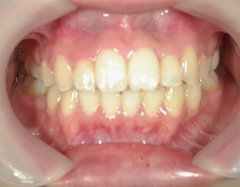

no.8_8495_治療前_左.jpgno.8_8495_治療前_正面.jpgno.8_8495_治療前_右.jpg

no.8_8495_治療後_左.jpgno.8_8495_治療後_正面.jpgno.8_8495_治療後_右.jpg